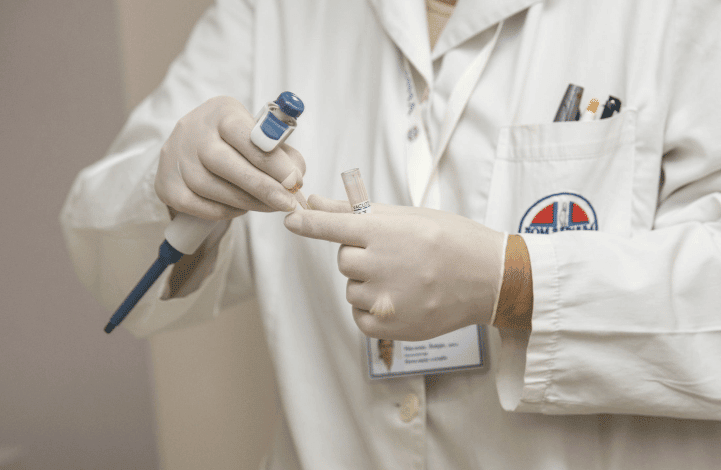

Dapatkan Layanan Medis yang Nyaman dan Terpercaya, Fasilitas Lengkap, Konsultasi dan Dokter jaga 24 Jam

Dipercaya 6309+